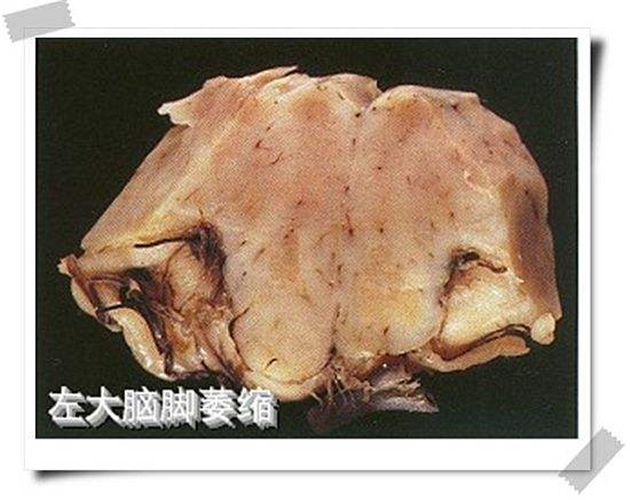

左大腦腳腦萎縮